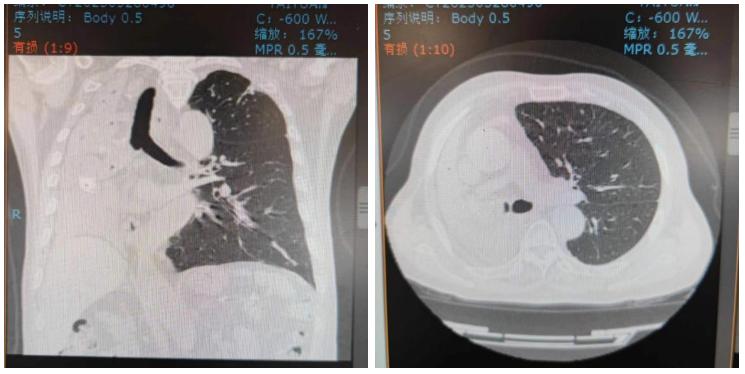

近日,北大医院太原医院(太原市中心医院)呼吸与危重症医学科汾东病区介入团队成功为一例肺癌致右主支气管完全梗阻,伴右肺不张的80岁高龄患者实施了经气管镜的肿瘤微波消融治疗术,手术成功打通右主支气管,保障患者通气功能,并置入Y型支架,防止肿瘤生长再次堵塞气道。术后,患者呼吸困难的症状得到改善,生存质量明显提高。

▲术前CT